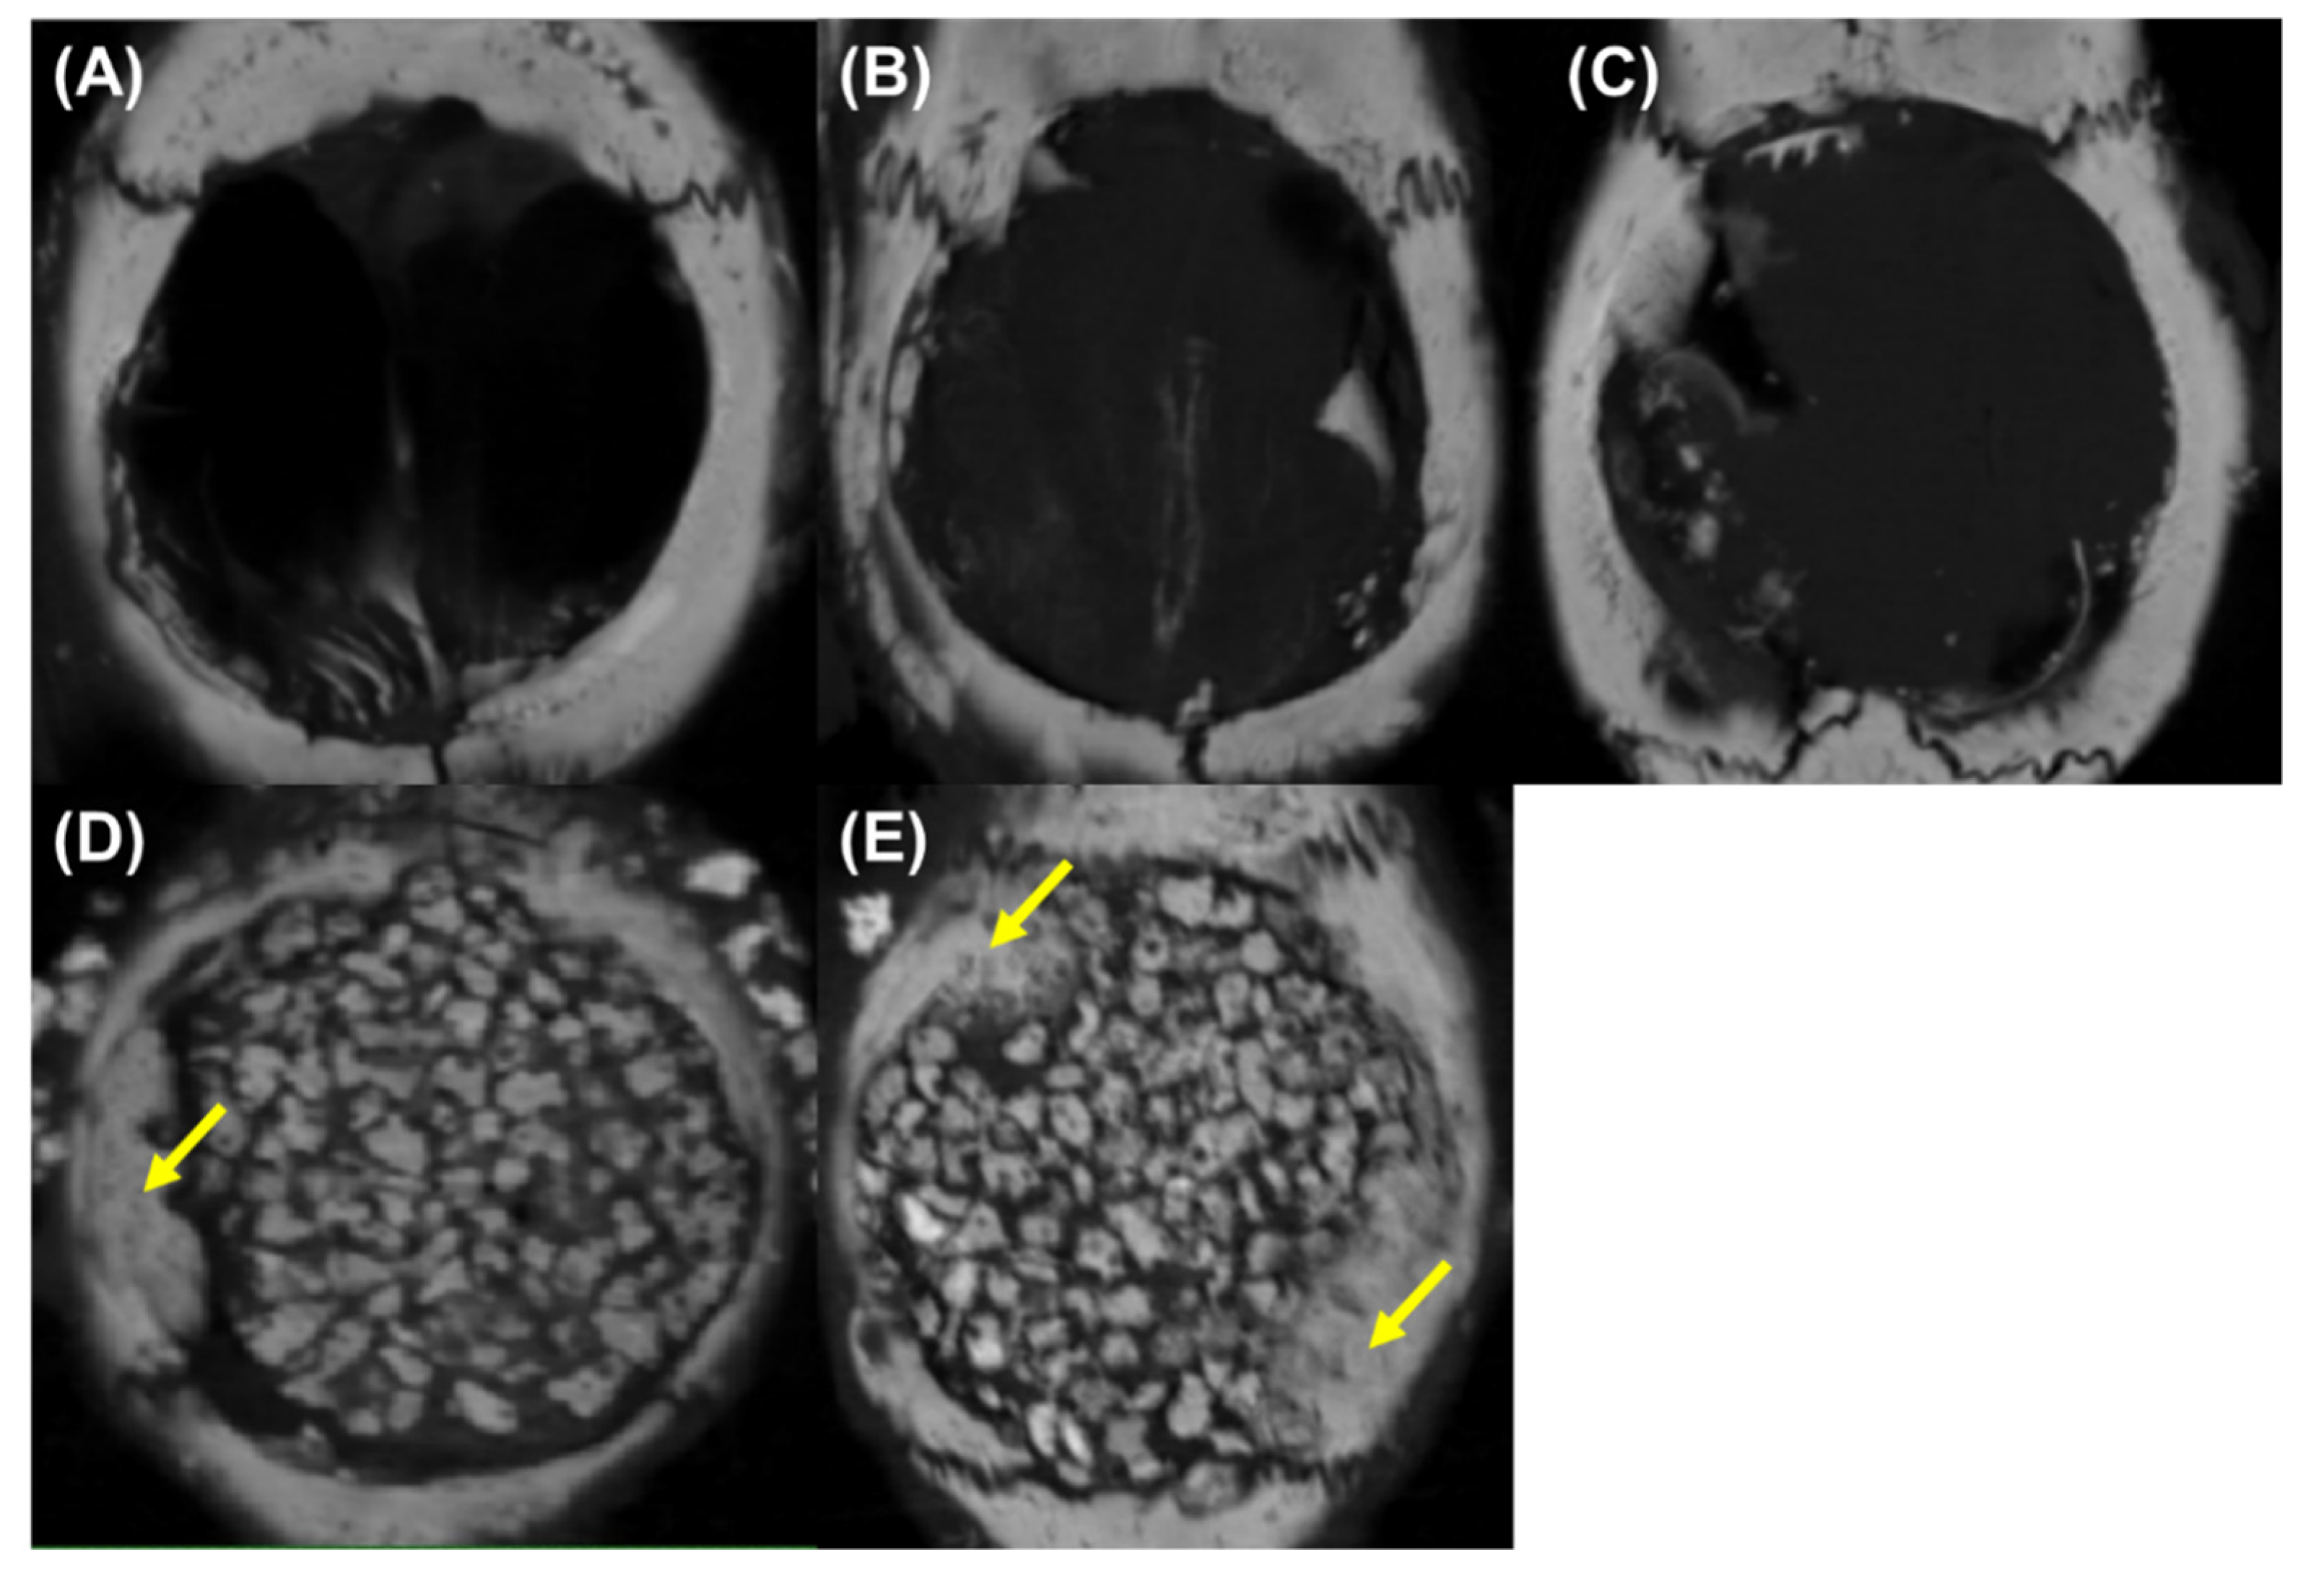

Figure 11 shows the reconstructed CT images. Although small bone was found in the defect, sponge, and GS groups, it was insufficient to be considered bone regeneration (Figure 12A–C). The α-TCP/GS group showed considerable residual α-TCP (Figure 12D); the α-TCP/GS + DFAT group showed bone regeneration from the edge of the defect (Figure 12E). Figure 12 presents µ-CT 3-D reconstructed images and the BMD distribution map. Each experimental group was analyzed at 4 weeks’ post-surgery; the BMD of each group is displayed in the 3-D map. High, middle, and low BMD are indicated on the color scale by blue and green, orange and yellow, and red and purple. Lesser bone regeneration was observed in the bone defect group; similarly, bone regeneration was rarely observed in the GS and the GS + DFAT (Figure 13A–C) groups. Several α-TCP granules persisted, with moderate new bone being observed at the edge of the defect (Figure 13D). In the α-TCP/GS+ DFAT group, new bone formed from the margin of the defect that displayed high BMD; the BMD value was similar to that of the mother bed bone. In addition, BMD images demonstrated that the α-TCP granules were bound to the adjacent α-TCP granules and resorbed (Figure 13E).

Figure 12.

Reconstructed image of CT (A) defect group, (B) GS group, (C) GS + DFAT group, (D) α-TCP/GS group, and (E) α-TCP/GS + DFAT group α-TCP/GS, composite gelatin sponge; GS, gelatin scaffolds; and DFAT, dedifferentiated fat cell. The yellow arrows indicate to new bone.

We performed quantitative image analysis of newly developed bone (Figure 14). There were no significant differences in RV/TV between the defect only, GS, and GS + DFAT. α-TCP/GS + DFAT demonstrated 56.95% RV/TV, which was the highest in the groups tested.